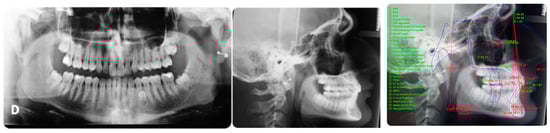

Figure 2 panoramic and CBCT showing the moderate palatal 2.3 impaction. Lateral X-rays confirming a Class I skeletal and dental malocclusion with deep bite.

Figure 2.

Cephalometric analysis, panoramic and CBCT of the first patient. Lateral X-rays confirming a Class I skeletal and dental malocclusion with deep bite.